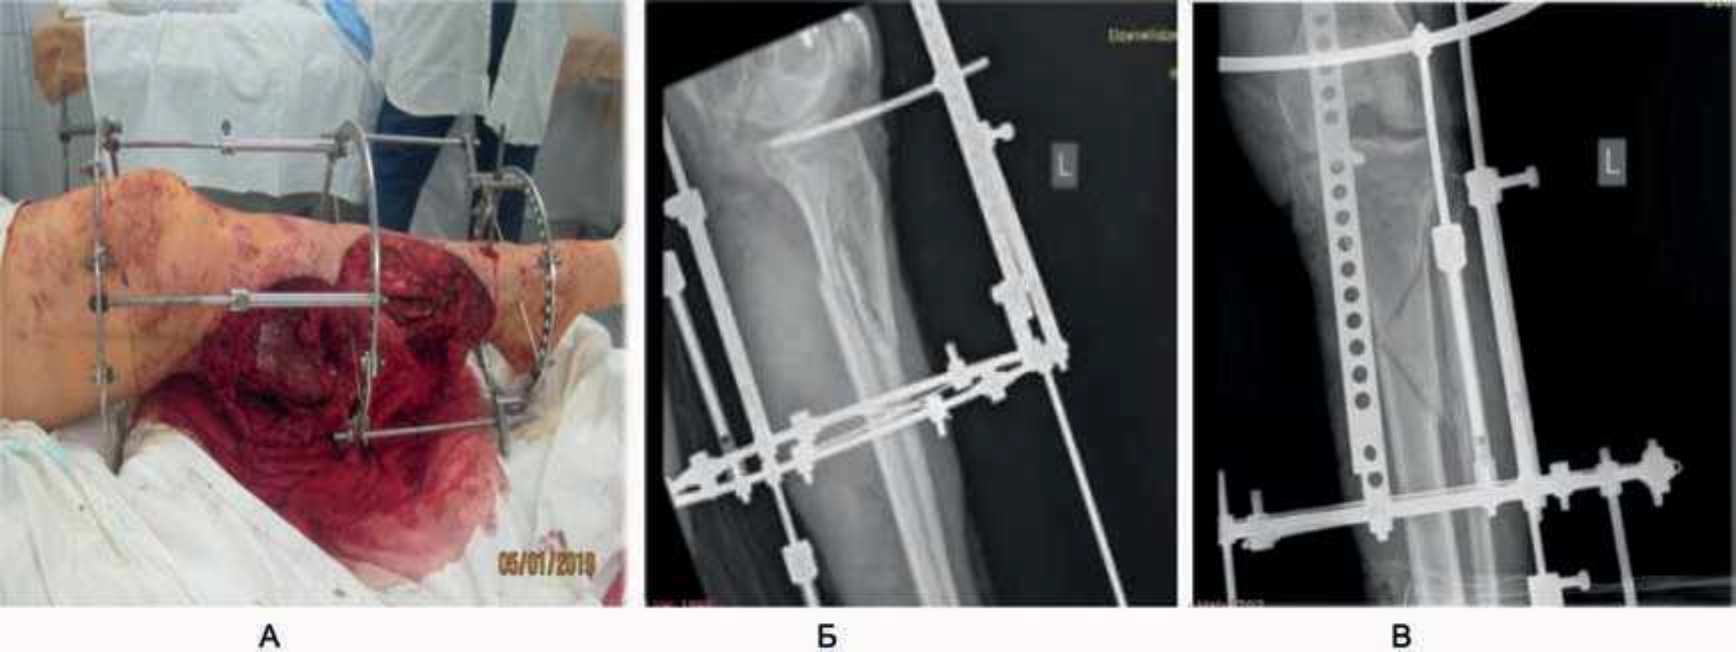

«Автомобильная травма. Открытый оскольчатый (по Густило IIIв) перелом верхней трети левой большеберцовой кости и нижней трети малоберцовой кости. Обширная открытая отслойка кожи левого бедра и голени. Закрытая ограниченная отслойка кожи по наружной поверхности правой голени» (рис. 10). Этапы хирургического лечения представлены на рис. 11, 12, результат восстановления кожного покрова – полное приживление трансплантата – на рис. 13. В течение 1 года пациентка носила компрессионное белье, занималась реабилитацией, в результате – восстановление движения в суставах левой нижней конечности в полном объеме (рис. 14).

Рис. 11. 1-е сутки: 1-й этап операции – металлоостеосинтез. Установка металлоконструкции (А), рентгеновский снимок, прямая (Б) и боковая проекция (В).